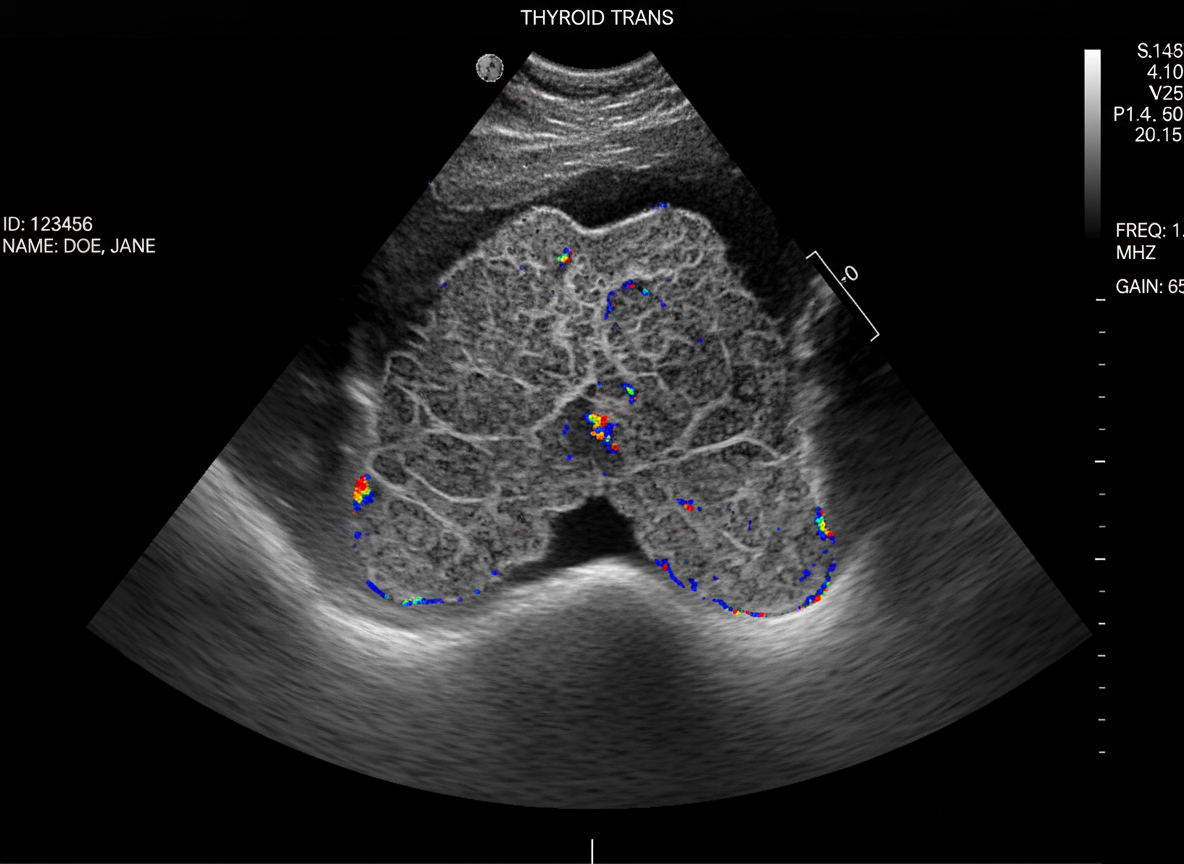

초음파 검사나 세침흡인 조직검사 같은 간단한 검사로도 충분히 확인할 수 있답니다.

갑상선암은 주로 갑상선 초음파 검사를 통해 결절을 확인하고,

의심스러운 결절이 발견되면 세침흡인 조직검사를 통해 암세포 유무를 확진해요.